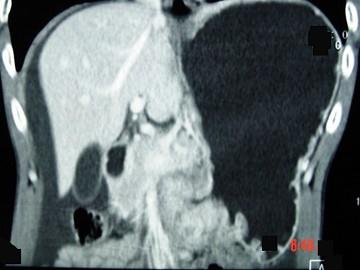

问题 男,65岁,中上腹痛腹胀、消瘦、乏力、纳差,影像检查如图,最可能的诊断是 ( )

选项 A.胃间质瘤 B.萎缩性胃炎 C.肥厚性胃炎 D.胃窦癌 E.胃淋巴瘤

答案 D